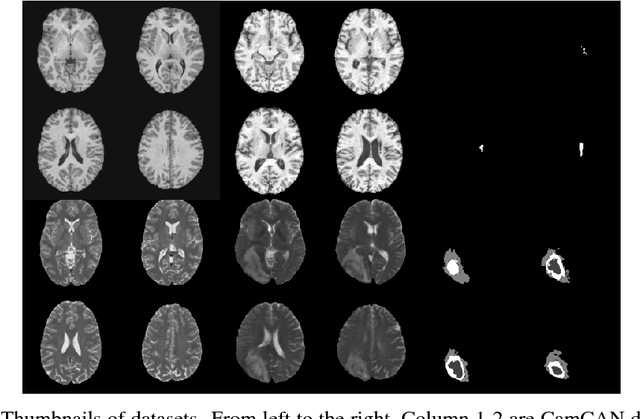

Abstract:Recent advances in deep learning led to novel generative modeling techniques that achieve unprecedented quality in generated samples and performance in learning complex distributions in imaging data. These new models in medical image computing have important applications that form clinically relevant and very challenging unsupervised learning problems. In this paper, we explore the feasibility of using state-of-the-art auto-encoder-based deep generative models, such as variational and adversarial auto-encoders, for one such task: abnormality detection in medical imaging. We utilize typical, publicly available datasets with brain scans from healthy subjects and patients with stroke lesions and brain tumors. We use the data from healthy subjects to train different auto-encoder based models to learn the distribution of healthy images and detect pathologies as outliers. Models that can better learn the data distribution should be able to detect outliers more accurately. We evaluate the detection performance of deep generative models and compare them with non-deep learning based approaches to provide a benchmark of the current state of research. We conclude that abnormality detection is a challenging task for deep generative models and large room exists for improvement. In order to facilitate further research, we aim to provide carefully pre-processed imaging data available to the research community.